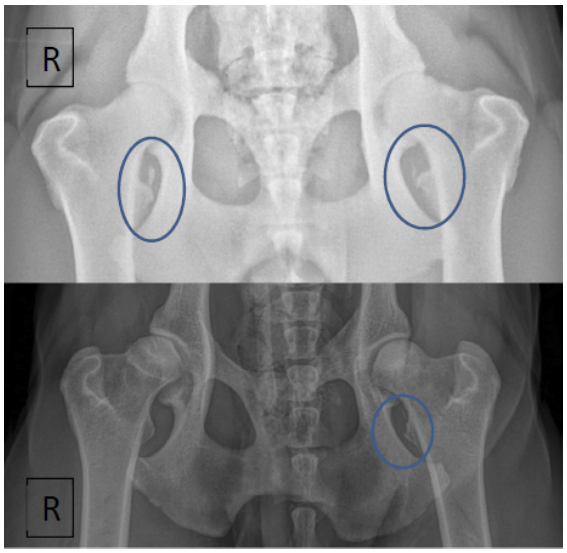

Clinical Evaluation of Iliopsoas Strain with Findings from Diagnostic Musculoskeletal Ultrasound in Agility Performance Canines – 73 Cases